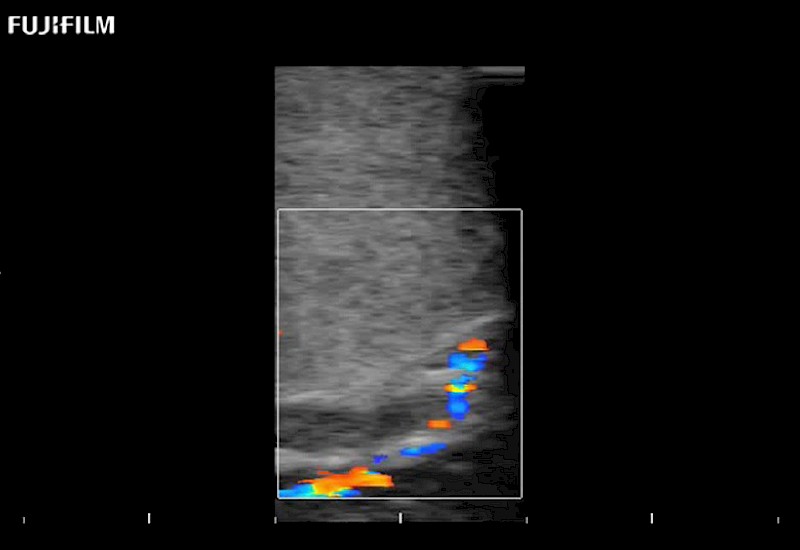

Multi-Parametric imaging modalities

Extraordinary high-resolution digital imaging

Our dedication to neurosurgery allows us to offer superior image quality, outstanding system reliability and intuitive use of cutting edge technology.